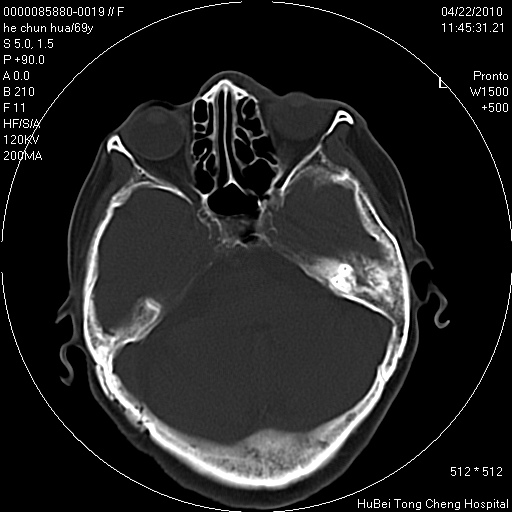

标题: CT25937:女,69Y

硬腭部包块十余年,渐进性增大。